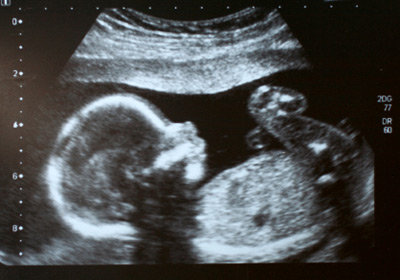

Ultraschallbilder Schwangerschaft